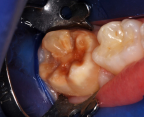

A 9-year-old presented with hypoplasia, hypocalcification, and caries.

Figure 1

A 9-year-old boy had a partially erupted mandibular first molar with much hypocalcification of the occlusal surface and a large caries lesion involving the occlusal and buccal surfaces (Figure 1). The patient complained of continuing sensitivity to cold stimulus and air inspiration. Because the tooth was only partially erupted, consideration for stainless steel crown full coverage had to be delayed. As an interim repair, it was decided to debride the carious tooth substance and place a light-hardened calcium silicate/mineral trioxide aggregate (MTA) liner, followed by a bonded restoration. After inferior alveolar block anesthetic injection and cotton roll isolation, cavity outline form was cut using a high-speed, water-cooled, medium-grit cylindrical diamond bur (Figure 2). Insufficient eruption precluded use of a rubber dam. A large, round bur at slow speed was used to debride the carious enamel and dentin. The prepared surfaces were swabbed for two 60-second applications of a 5% glutaraldehyde/HEMA solution for desensitization and disinfection of the preparation.6,7 Cavity liner was then injected and spread over the deepest sections of the cavity floor and hardened with the visible light beam (Figure 3). After a self-etching bonding agent was applied over the remaining enamel surfaces, without the need for any type of matrix, an RMGI bioactive ionic resin-based composite was injected, in one portion, into the preparation and spread over the four cusps using a ball burnisher. This restorative complex was then photo-polymerized using two 20-second exposures of the visible light beam (1,200 mW/cm2). The restoration was trimmed and finished with large, round diamond burs at slow speed, and occlusion was evaluated with articulating paper and adjusted.